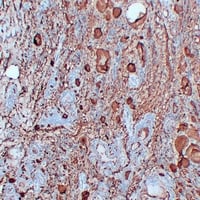

(Immunohistochemical analysis of Thyroglobulin staining in human papillary thyroid carcinoma formalin fixed paraffin embedded tissue section. The section was pre-treated using heat mediated antigen retrieval with sodium citrate buffer (pH 6.0). The section was then incubated with the antibody at room temperature and detected using an HRP conjugated compact polymer system. DAB was used as the chromogen. The section was then counterstained with haematoxylin and mounted with DPX.)